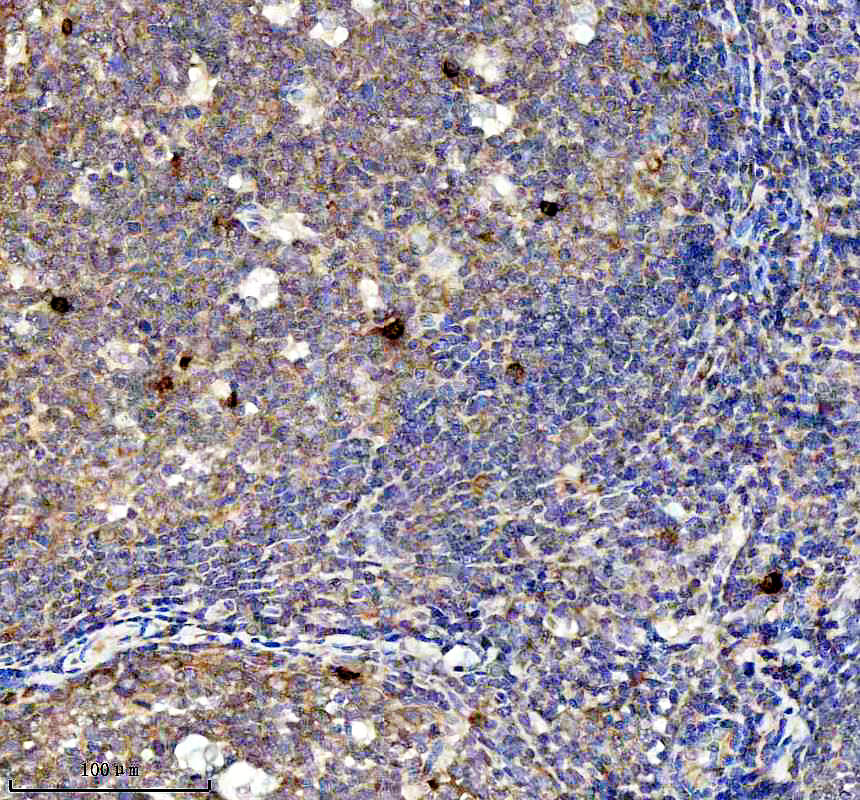

IHC analysis of BNIP3L using anti-BNIP3L antibody (BM5174) .

BNIP3L was detected in a paraffin-embedded section of human tonsil tissue. The tissue section was incubated with rabbit anti-BNIP3L Antibody (BM5174) at a dilution of 1:200 and developed using HRP Conjugated Rabbit IgG Super Vision Assay Kit (Catalog # SV0002) with DAB (Catalog # AR1027) as the chromogen.

IHC analysis of BNIP3L using anti-BNIP3L antibody (BM5174) .

BNIP3L was detected in a paraffin-embedded section of human tonsil tissue. The tissue section was incubated with rabbit anti-BNIP3L Antibody (BM5174) at a dilution of 1:200 and developed using HRP Conjugated Rabbit IgG Super Vision Assay Kit (Catalog # SV0002) with DAB (Catalog # AR1027) as the chromogen.